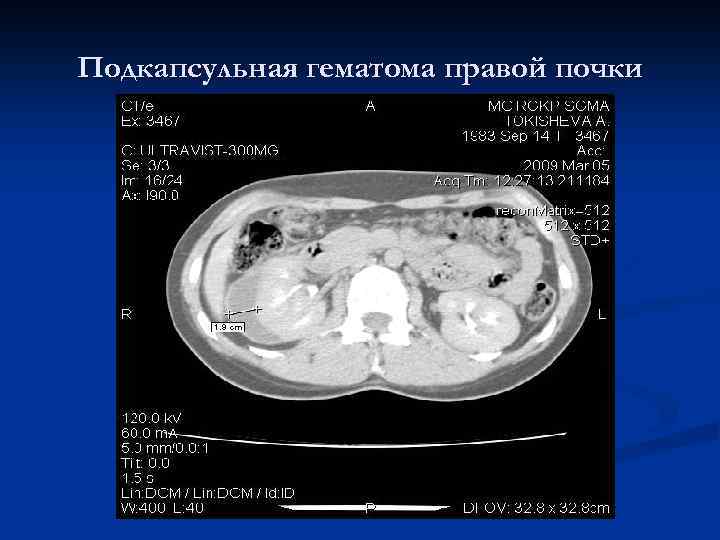

Подкапсульная гематома правой почки